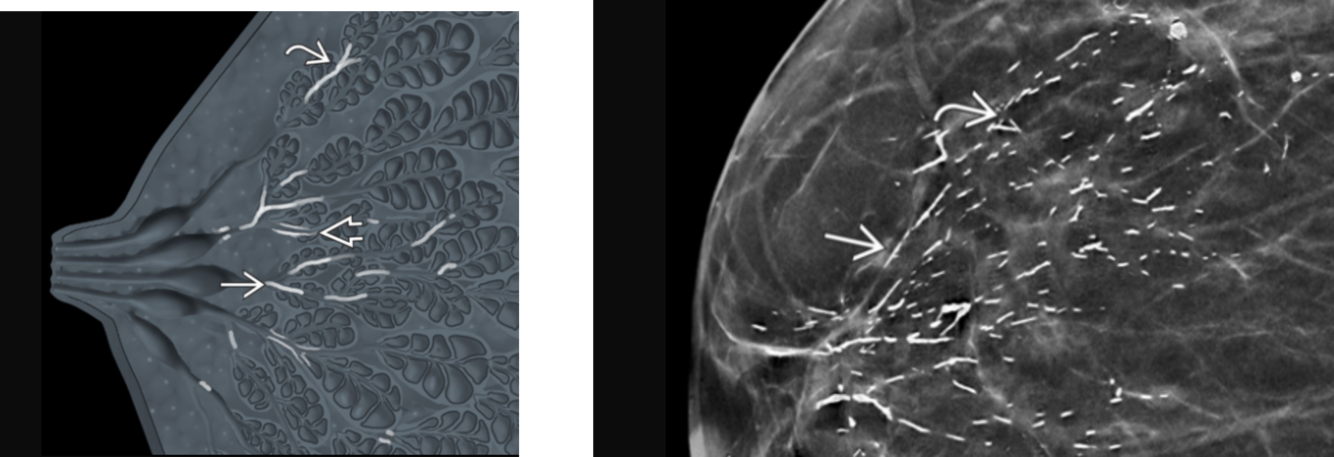

dermal calcs:

most common in the parasternal area and inframammary fold